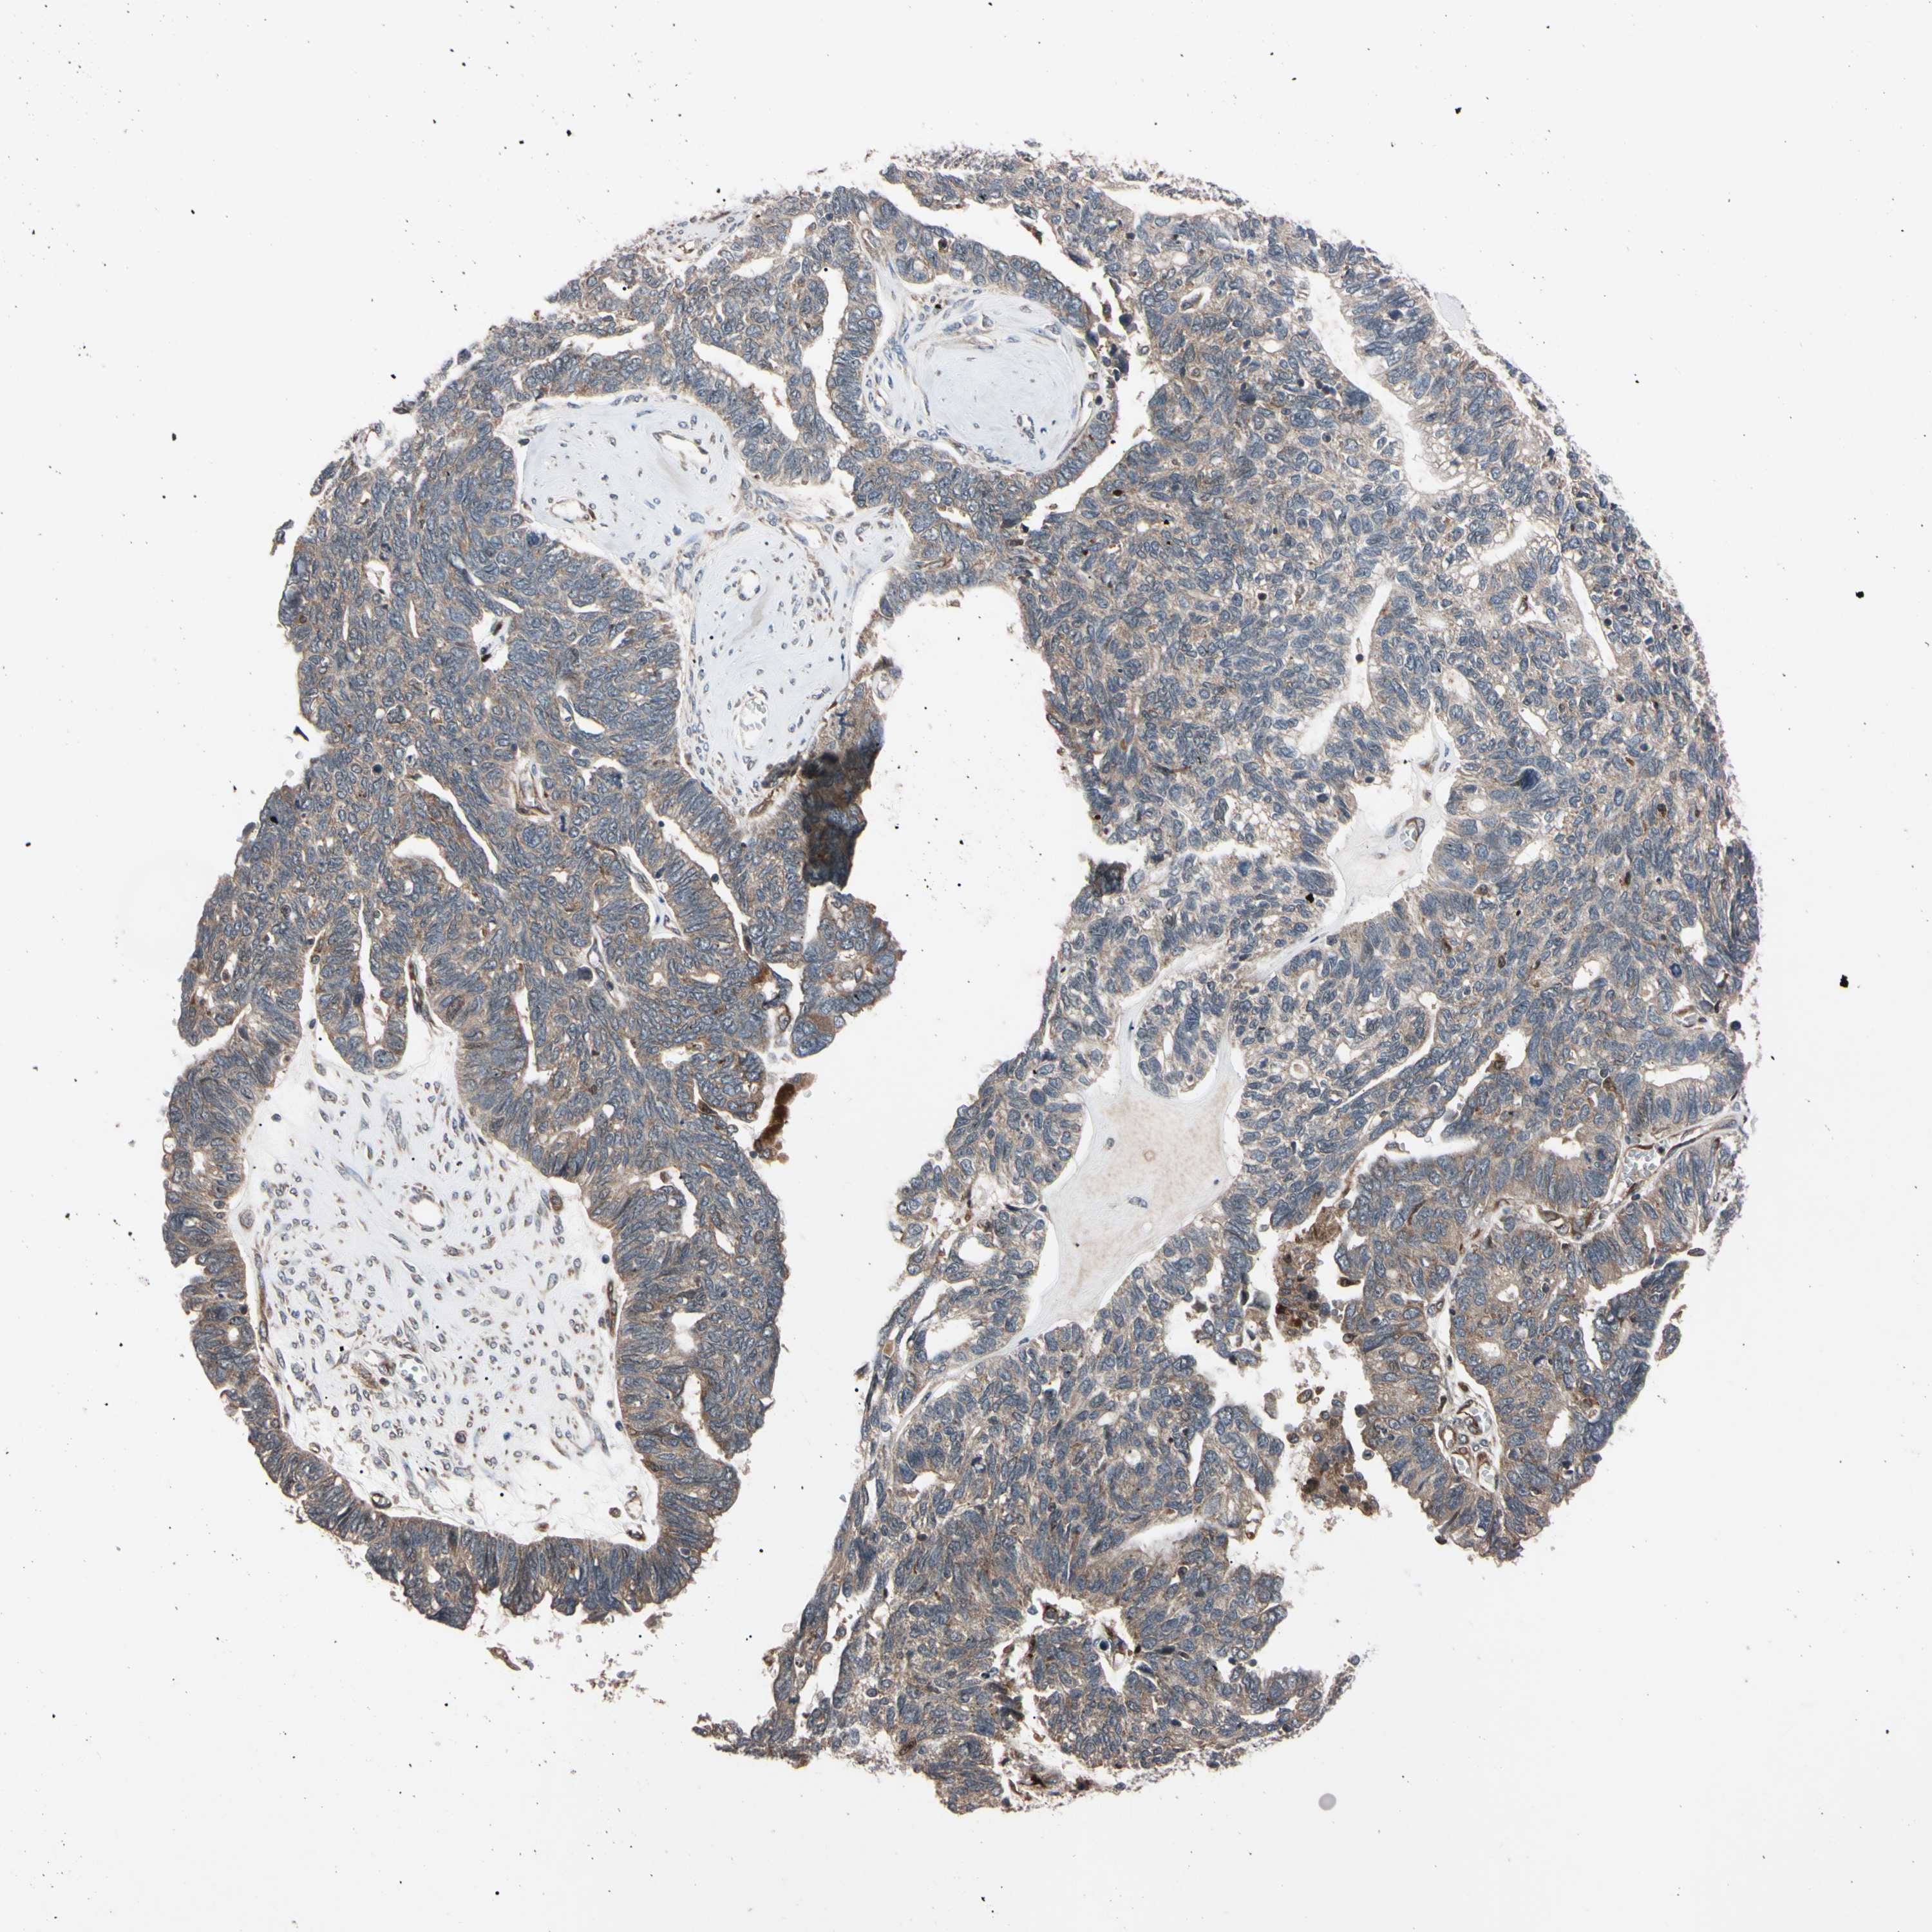

OVARIAN CANCER - Protein expressioni

A mouse-over function shows sample information and annotation data. Click on an image to view it in a full screen mode. Samples can be filtered based on level of antibody staining by selecting one or several of the following categories: high, medium, low and not detected. The assay and annotation is described here.

Note that samples used for immunohistochemistry by the Human Protein Atlas do not correspond to samples in the TCGA dataset.

Antibody stainingi

Antibody staining in the annotated cell types in the current human tissue is reported as not detected, low, medium, or high, based on conventional immunohistochemistry profiling in selected tissues. This score is based on the combination of the staining intensity and fraction of stained cells.

Each image is clickable and will lead to virtual microscopy that enables deeper exploration of all samples and also displays staining intensity scores, fraction scores and subcellular localization as well as patient and tissue information for each sample.

Antibody HPA020870

Antibody CAB010890

Cystadenocarcinoma, mucinous, NOS